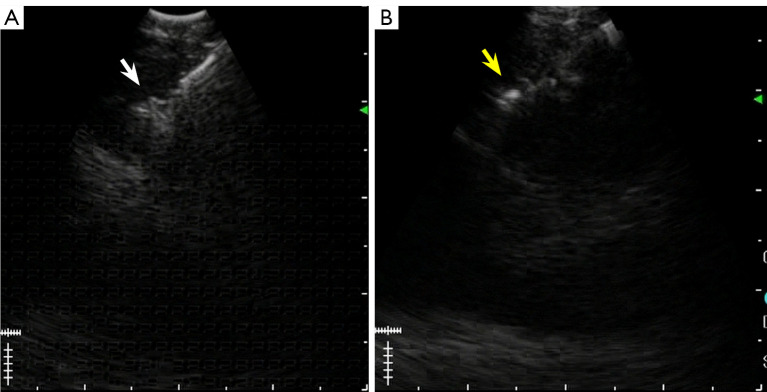

Case description: An 83-year-old woman with lung adenocarcinoma harboring MET exon 14 skipping mutation presented with right upper lobe nodules and bilateral mediastinal lymphadenopathy. The initial EBUS-TBNA yielded insufficient specimens for molecular testing. Subsequent EBUS-IFB and mediastinal cryobiopsy provided sufficient specimens for definitive diagnosis. Twenty-nine days after the procedure, computed tomography revealed rapid growth of the right upper lobe nodules and a tracheal mass at the biopsy site, consistent with NTS. Despite this complication, the patient demonstrated a marked response to tepotinib therapy, with significant regression of both the lung and tracheal lesions.